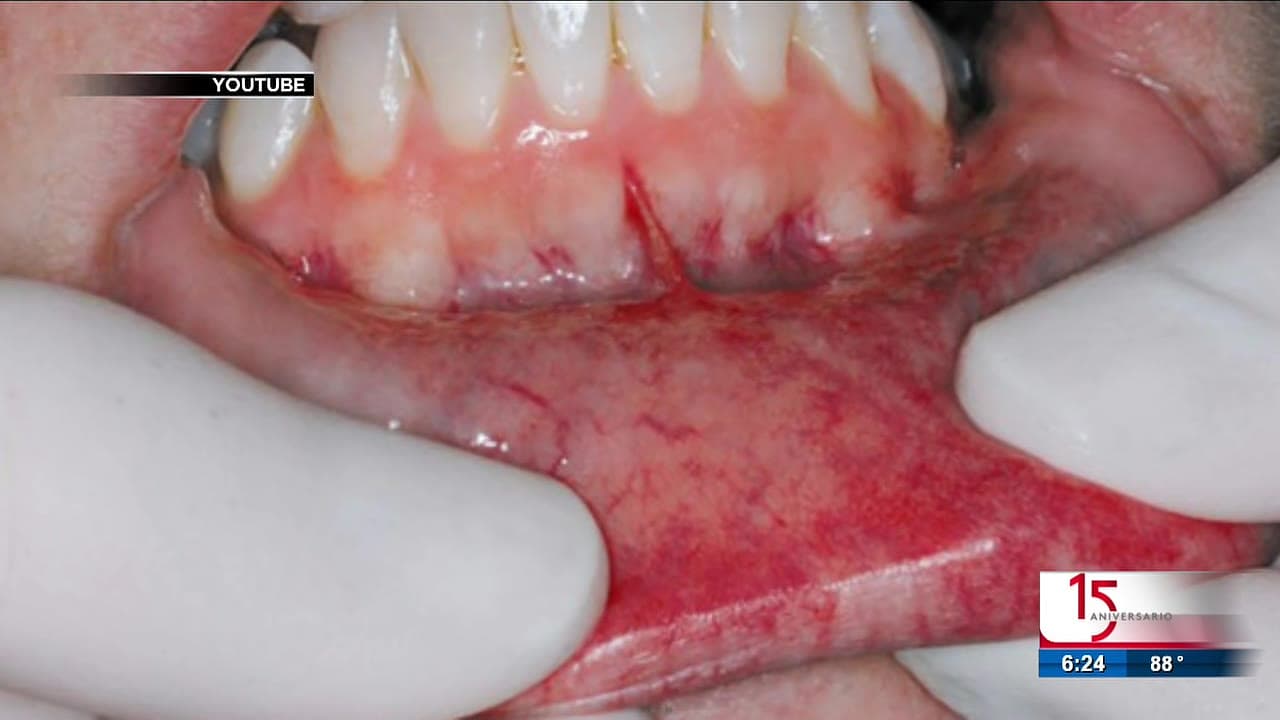

Reportan aumento en cáncer bucal en los últimos años

Según expertos, factores como fumar y beber alcohol en exceso, además del VPH, aumentan el riesgo de este tipo de cáncer.